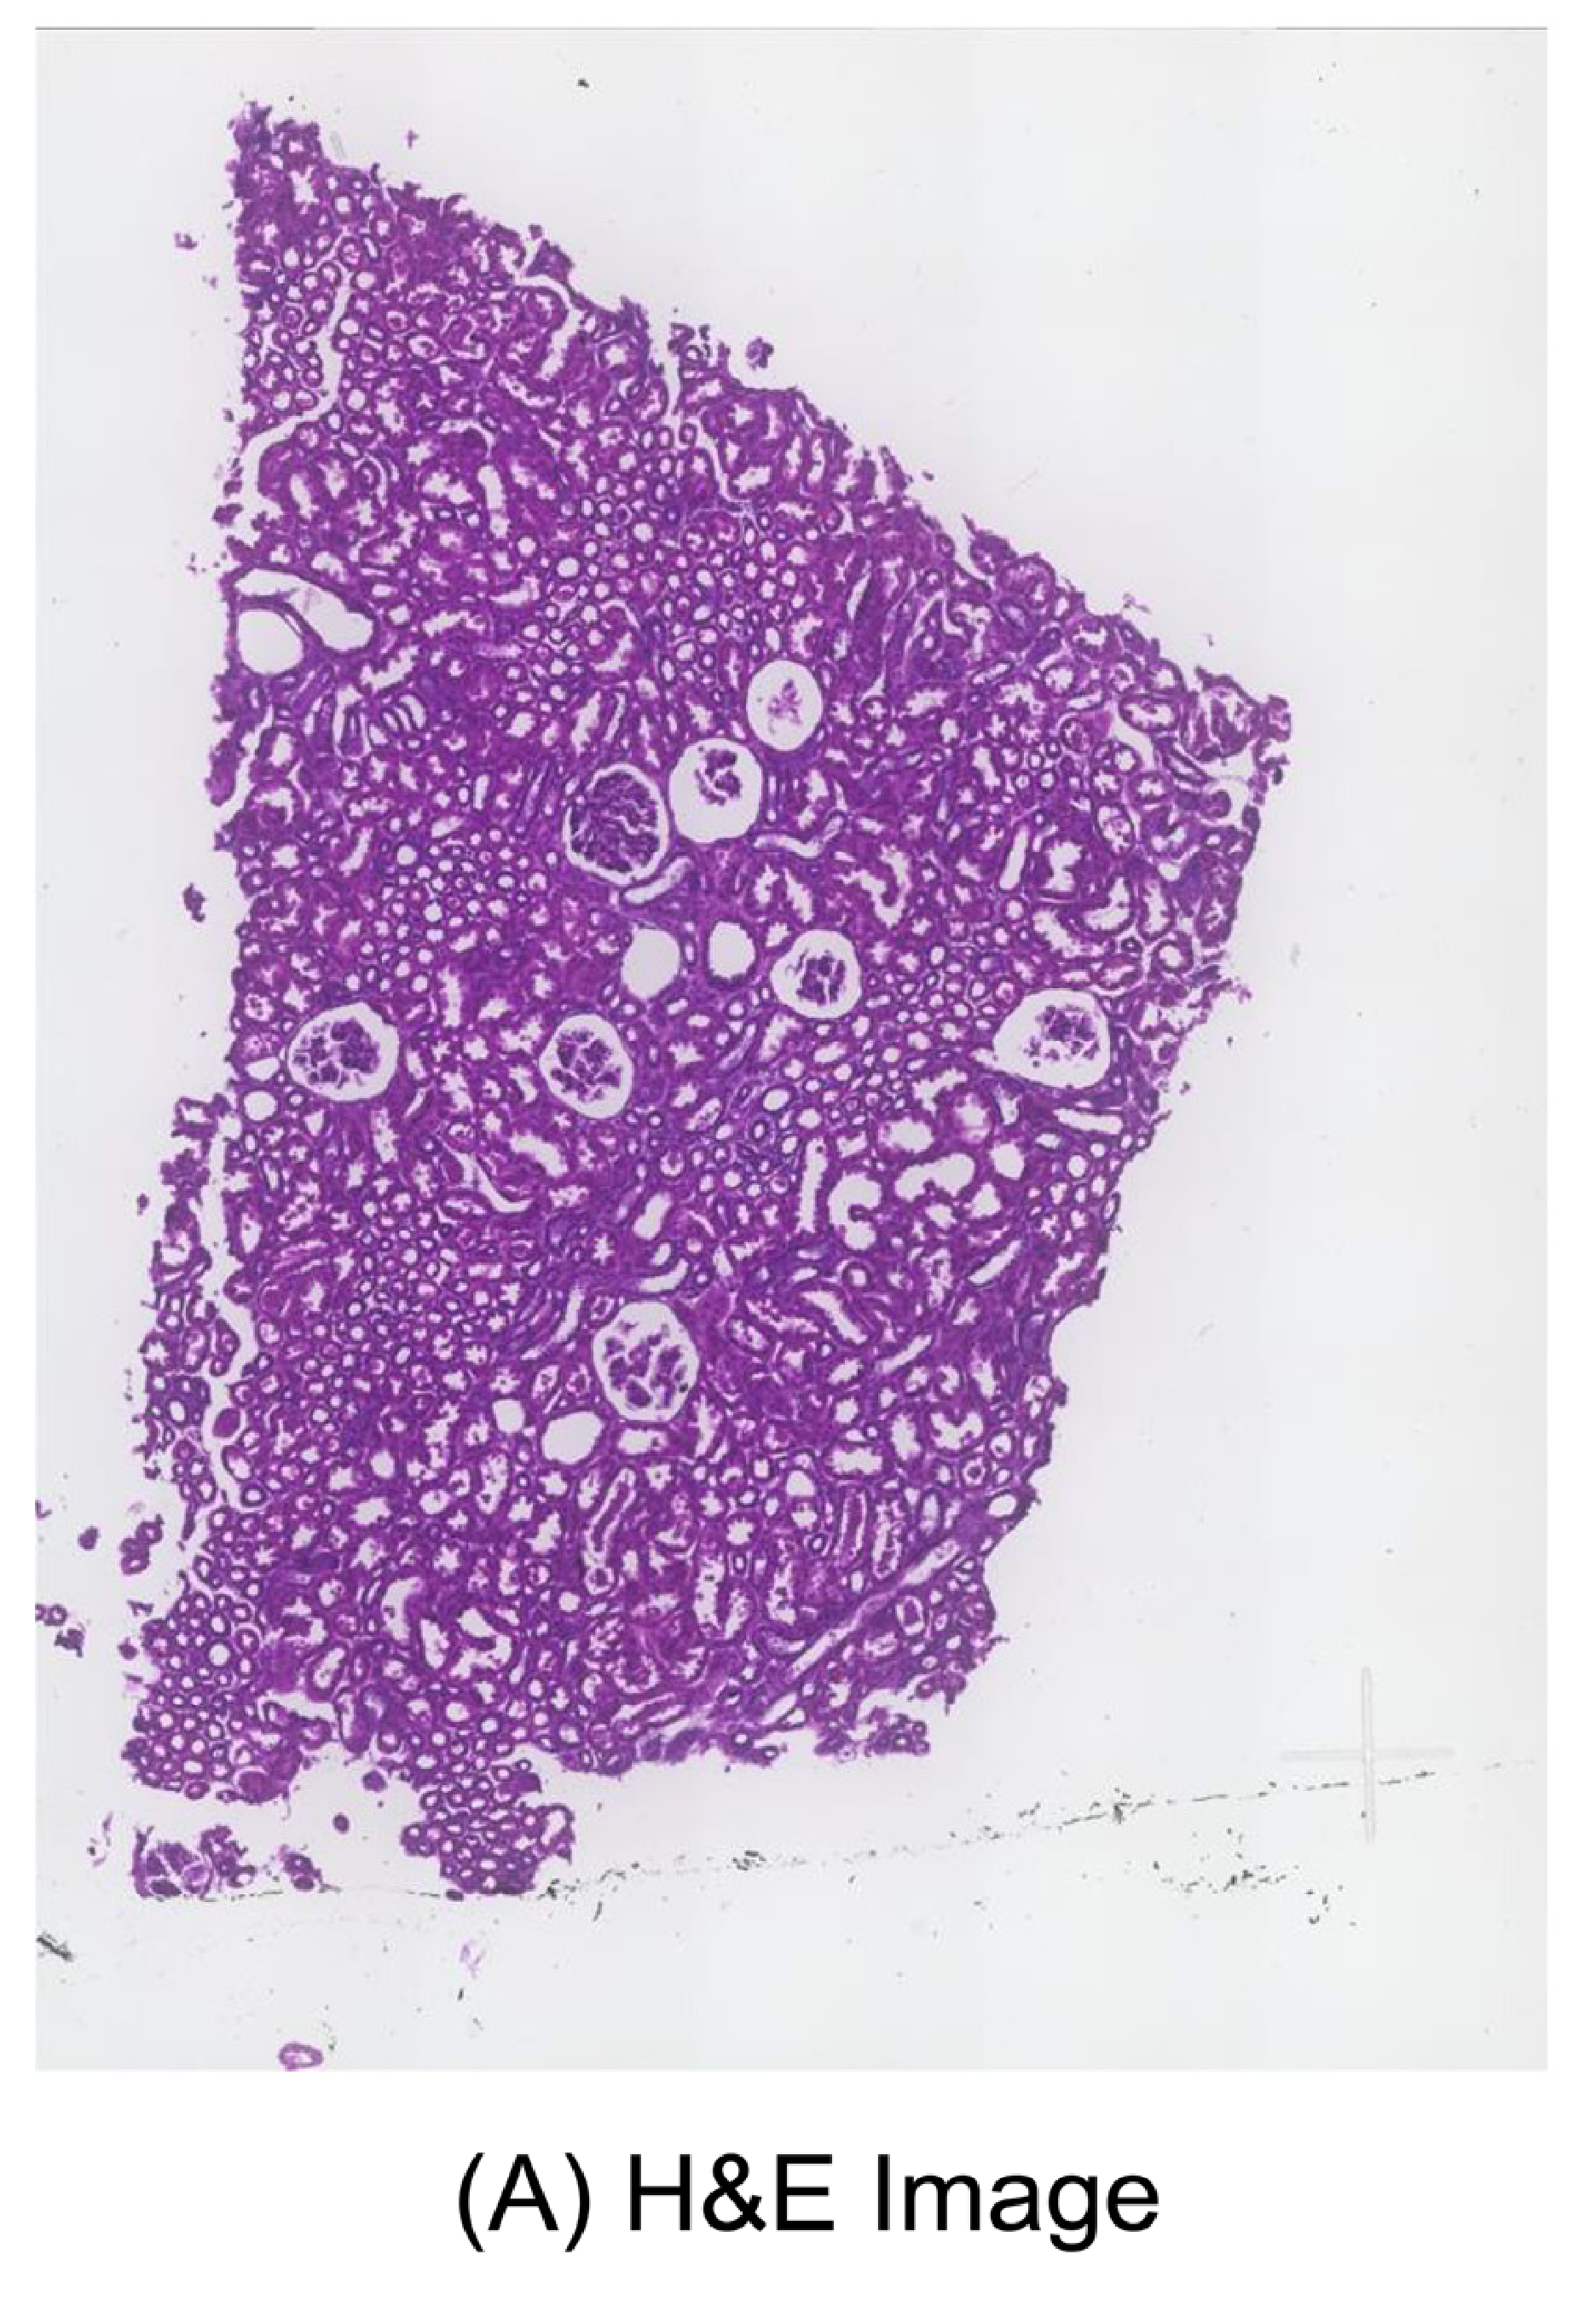

Wei R. et al. - 2022

Spatial charting of single-cell transcriptomes in tissues

Where are tumor regions located within the spatial architecture of a tissue section?